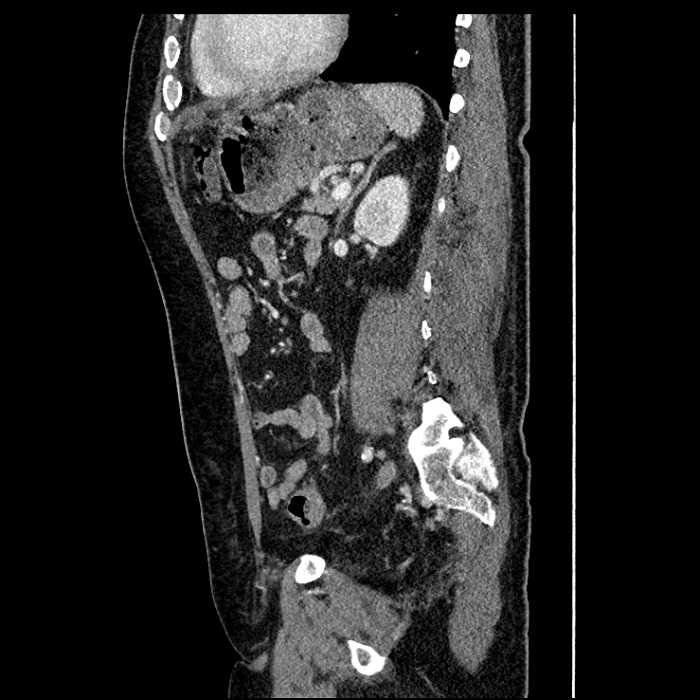

Age: 63

Sex: Male

Indication: Abdominal pain

• Large fluid density structure in hepatic segments 7 and 8 measuring 10 x 7 x 7 cm with internal septation and circumferential ill-defined low density compatible with edema

• Peripherally enhancing subcapsular collections along the anterior margin of the left hepatic lobe measuring 3 x 1 cm and 2 x 1 cm

• Clearly marginated fluid density structure in segment 7 and several other scattered tiny hypodensities, which likely represent cysts

• Mild mural thickening of a segment of the sigmoid colon with adjacent fat stranding and a 1.5 cm fluid and gas collection along the tip of an inflamed diverticulum

• Loss of the normal fat plane between this collection and adjacent loops of small bowel, which demonstrate mural thickening

• High grade stenosis of the left common iliac artery, with the left internal and external iliac arteries remaining patent

Acute sigmoid diverticulitis complicated by a small contained perforation and a large abscess in the right hepatic lobe. Additional small subcapsular abscesses along the anterior margin of the left hepatic lobe.

Additionally, loss of the normal fat plane between the peridiverticular collection and adjacent thickened loops of small bowel raises the potential for an enterocolonic fistula.

High grade stenosis of the left common iliac artery. The left external and internal iliac arteries are patent.

• The classic CT imaging appearance is a double target sign with internal low density surrounded by an internal enhancing rim (capsule) and a low density external rim (edema)

Hepatic abscess showing the double target sign with low density internally surrounded by a thin inner enhancing rim (red arrow) and ill-defined outer low density rim (yellow arrow). Blue arrow indicates an internal septation. Red arrows: additional smaller subcapsular abscesses. Red arrow: focal contained perforation associated with diverticulitis.